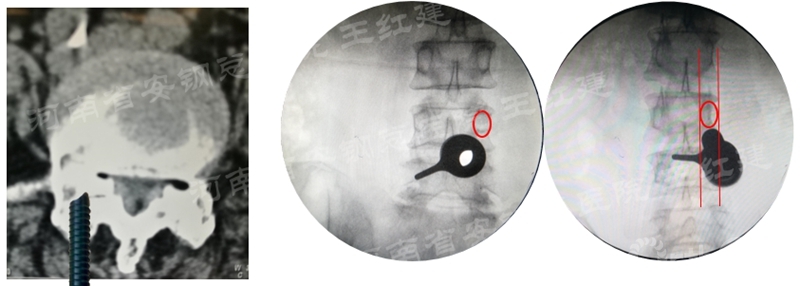

应用通道技术进行植入融合时,首先要更换工作套管,通过枪钳、抓钳的应用处理椎间盘,接着进行自体骨或同种异体骨及cage植入,并通过C臂透视确定试模型号放置融合器,最终完成植骨融合。

确定融合器位置

在固定的步骤可以先期进行经皮螺钉置入,再进行融合器的置入,进而实现充分固定。

手术步骤:先期经皮螺钉置入、再进行融合器的置入